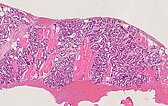

The histopathological overview image (40× magnification; H&E stain) of the punch cylinder of the lesion shows skeletal muscle diffusely interspersed by lobularly arranged capillary proliferates and some fat cells (white, roundish large cells), which are indicative of partial involution already occurring.

At 90× magnification (H&E stain), lobulation of the vascular proliferates is suggestive of a benign vascular process. The enclosed skeletal muscle fibers are overgrown but not destroyed, as would be the case in a malignant process. Intermingling with pre-existing tissue structures without their alteration is typical of infantile hemangiomas.